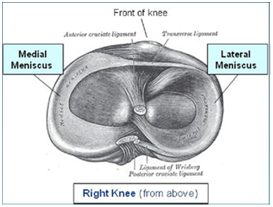

那么什么是半月板呢,它为什么会损伤呢?你知道吗?其实在人膝关节上下两块关节骨之间内外侧各有一个垫圈。在正常情况下其形状就象两个月牙,所以被称为半月板。它就像一个纤维垫,非常有弹性,充填于股骨关节面与胫骨关节面之间,有吸收震荡、缓冲压力、增强膝关节稳定、防止膝关节损伤,延缓膝关节老化的作用。

正常的半月板